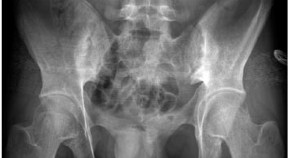

• The authors present the case of a 49-year-old man diagnosed with chronic unilateral sacroiliitis who did not respond to conventional therapy with corticosteroids and NSAIDs. A single intra-articular injection of the tumor necrosis factor inhibitor infliximab resulted in gradual and steady improvements in pain, stiffness and inflammation.

• Finbar D O'Shea

• Nigil Haroon

• Robert D Inman

Case Study